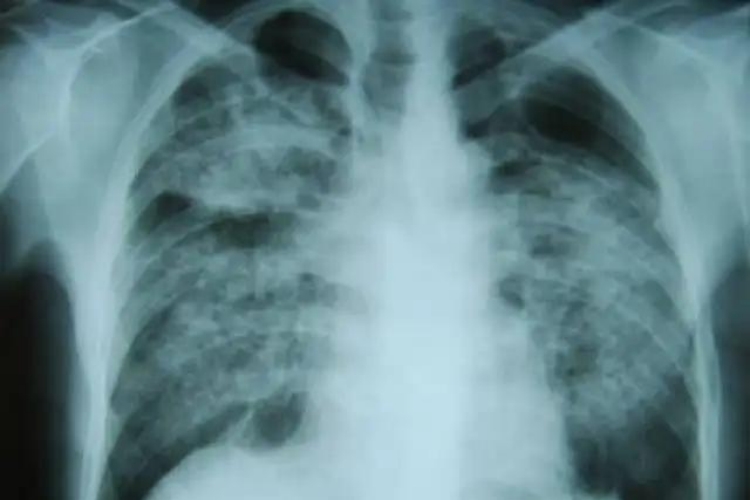

尘肺病是由于长期吸入粉尘引起的肺组织弥漫性纤维化疾病,CT可见肺部有弥漫分布的阴影,解剖可见肺部呈灰黑色,表面有黑色斑点。

尘肺病的肺可呈灰黑色,表面有坚实的类圆形结节,结节境界清楚。在肺部可以看到尘斑分布,通常是灰黑色或黑色、质地坚韧的纤维性团块,影像学检查可见弥漫性纤维化表现。此外,患者可出现咳嗽、胸闷、疼痛、呼吸困难等症状。